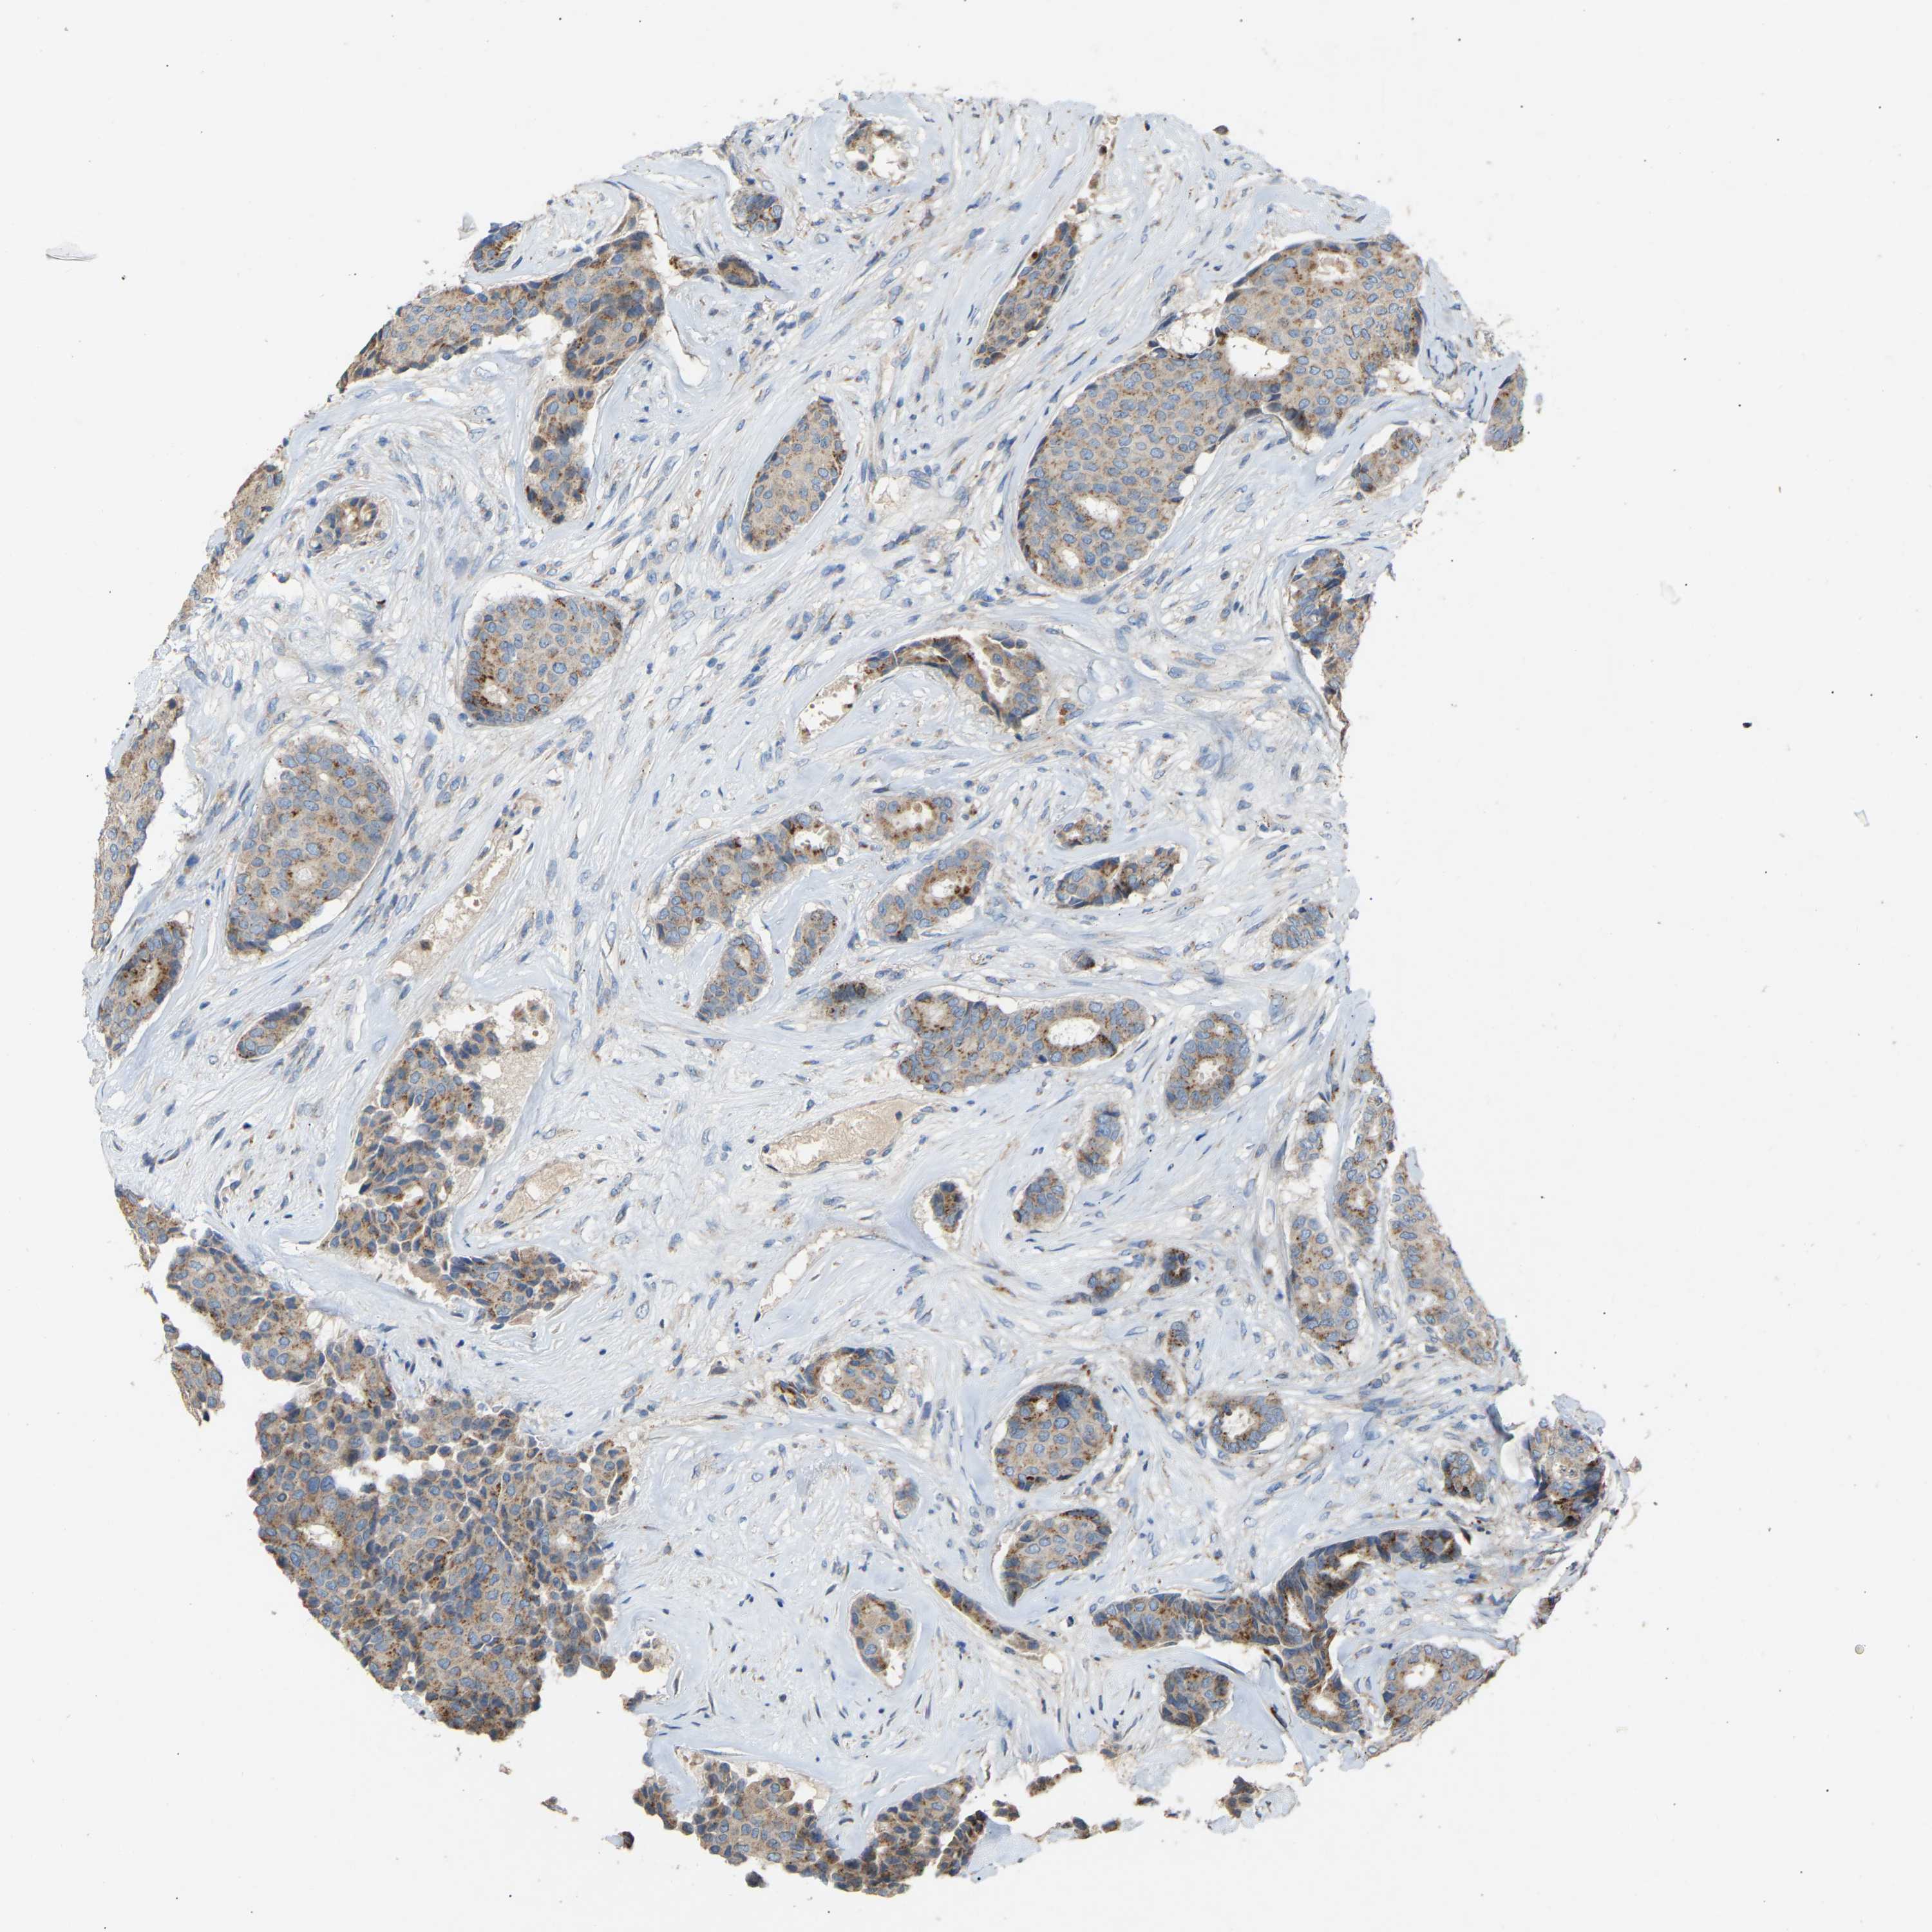

CANCER BREAST CANCER Show tissue menu

BRCA TCGA BRCA VALIDATION PROTEIN EXPRESSION

ANTIBODIES

AND

VALIDATION